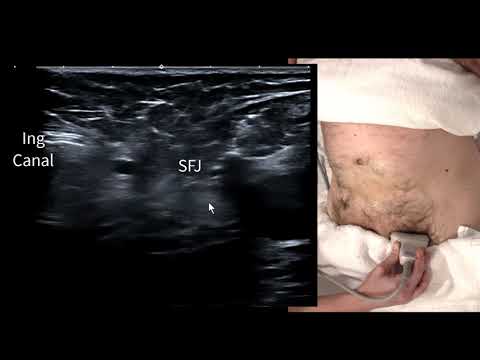

УЗИ паховой грыжи, часть 2

Учебное пособие по УЗИ: оценка паховой/бедренной грыжи | Radiology Nation

Бедренная грыжа + паховая грыжа, ультразвуковое сканирование в реальном времени для прямого и неп...